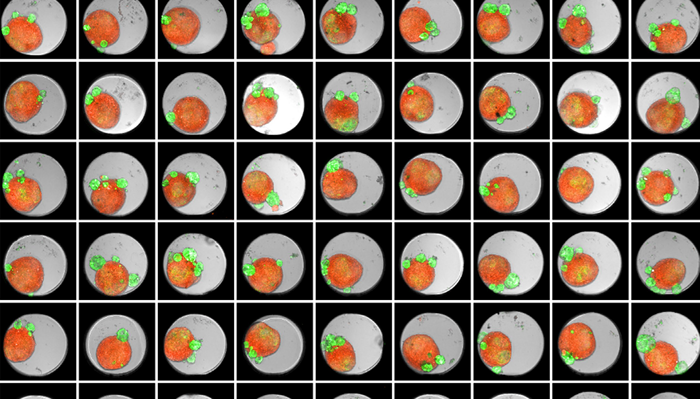

Thumbnail of an Akura 384™ well plate of 3D tumor co-culture microtissues - NCI-N87-GFP (green), NIH-RFP (red), Bright Field (gray)

Figure 1. Thumbnail of an Akura 384 well plate of 3D tumor co-culture microtissues - NCI-N87-GFP (green), NIH-RFP (red), Bright Field (gray). Image Credit: Yokogawa Life Science

Tumor spheroids were created by seeding an Akura 384 plate with a monodispersed mixture of GFP-expressing NCI-N87 (gastric carcinoma) and RFP-expressing NIH3T3-L1 (murine fibroblast) cells, which spontaneously formed spheroids through scaffold-free self-assembly over several days. After spheroid formation, selected wells containing tumor spheroids were treated with DMSO at 0.05, 0.5, or 5.0 μM Lapatinib for six days. The images were analyzed in 3D, with NCI-N87-GFP (tumor) and NIH-RFP (fibroblast) identified separately, and the volume of each spheroid measured.